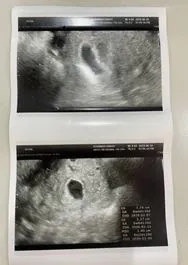

긴장되는 마음으로 순번을 기다린 후 초음파를 보았고, 무사히 아기집과 난황을 확인할 수 있었다.

123.JPG

아직 잔존하고 있는 물혹이 혹시라도 더 커지거나 터지게 되면 위험한 상황이 발생될 수 있다는 안내를 받았으나 물혹 상태가 나쁘지 않아 보이고 물혹을 갖은 채로 출산까지 잘하는 산모들이 많으니 크게 걱정하지 말라고 하셨다.